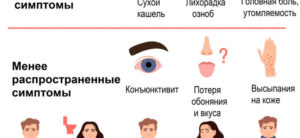

Легкая форма коронавируса: как протекает, симптомы, сколько длится, чем лечить?

Из этой статьи вы узнаете, что такое легкая форма коронавируса, каковы первые симптомы, как долго он длится, можно ли лечить в домашних условиях и какие лекарства используются. Что значит легкая форма коронавирусной инфекции Любое течение инфекции без пневмонии официально признано легкой формой коронавируса. На практике существует 4 формы Sars-Cov-2: латентная — без симптомов; мягкий — …